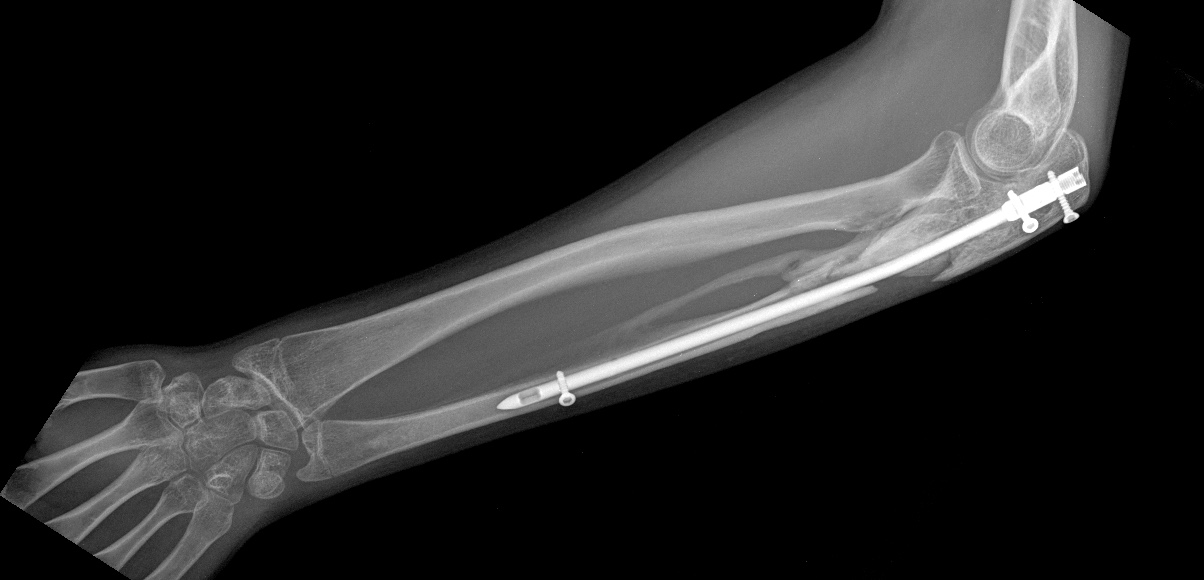

Возможно, и поменяет. Позволит оценить некоторые аспекты. Характер псевдоартроза, смещения и т.д. Вообще, как-то странновато - ложный сустав, два вывиха на одном сегменте и снимок в одной проекции?! Поскольку второй проекции дождаться не удалось, предложу следующий план решения проблемы: Удаление пластины, остеосинтез аппаратом, постепенная дистракция, чрезочаговая репозиция спицами с упорами оставшихся смещений. Дёшево и эффективно. Вторая проекция помогла бы детализировать некоторые моменты. Ниже очень похожий случай, пациент оперирован через 8 месяцев после травмы.

P.S. Вот она:

Мы бы удалили пластину. Аппаратом постепенно восстановили бы взаимоотношения. И заштифтовали бы локтевую кость, смоделировав стержень, чтобы он был напряжен в противоположную сторону тому, как сейчас выглядит локтевая кость, т.е. вогнутой стороной в сторону межкостного промежутка. Чтобы лучевая кость удерживалась натяжением межкостной мембраны. Пример в приложении. Тут был более свежий случай, поэтому вправилось одномоментно.